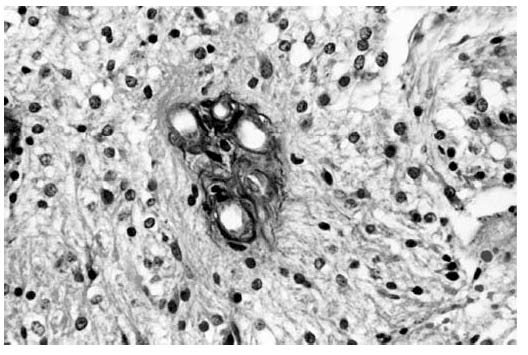

Většina tumorů této lokalizace jsou pilocytické a difúzní

astrocytomy (obrázek 1 a 2). Nádory chiasmaticko-hypothalamické

Obrázek 2 – Difúzní (G2) astrocytom, absence

bifázického vzhledu, H-E